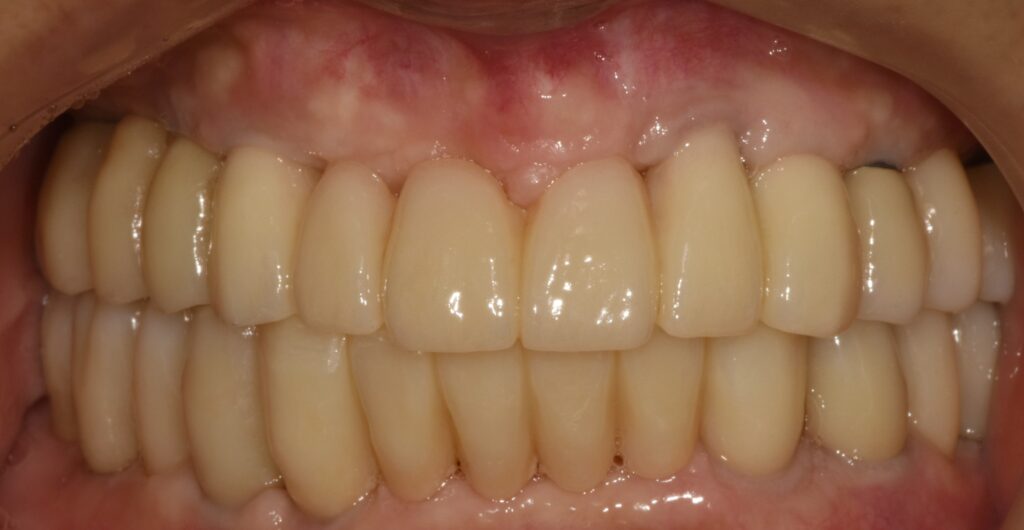

​사진 : 아래는 임플란트 보철이 즉시 들어갔고, 위에는 임시틀니를 이용해서 식사를 가능케 해드린 모습.

아래는 임플란트를 이용하여 즉시 임시 보철을 만들어 드렸고 (탈착 안 해도 되는 고정식 보철)

​위턱에는 전체 틀니를 만들어 드려서 바로 식사가 가능케 해드렸습니다.

임플란트 보철까지 깔끔하게 잘 올라간 모습을 볼 수 있습니다.